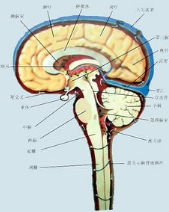

圖一 (2)髓外腫瘤:兒童期髓外腫瘤多位於骶尾部,常合併有椎管閉合不全局部皮膚可有顯著標誌如:皮下脂肪瘤血管瘤毛髮異常分布及皮毛竇,如圖1所示常見的腫瘤有:椎管內脂肪瘤、皮樣囊腫表皮樣囊腫、腸源性囊腫和畸胎瘤均系先天性發育異常引起可產生脊髓栓系綜合徵兒童骶尾區脂肪瘤侵犯範圍廣泛,可位於硬脊膜內外或包裹馬尾神經腫瘤與軟脊膜粘連緊密,並有纖維隔穿入髓內神經根性疼痛症狀少見,主要以肢體麻木和直腸膀胱括約肌功能障礙為主影像學有脂肪組織的特徵性表現,手術全切除困難皮樣囊腫和表皮樣囊腫除了有椎管內占位的一般表現外多因囊腫內容物的滲漏刺激導致反覆發作的腦膜炎。成人較為常見的髓外腫瘤神經纖維瘤和脊膜瘤在兒童期少見,多發生在患有神經纖維瘤病的患兒中,神經纖維瘤起源於感覺神經根腫瘤生長可導致椎間孔的擴大產生明顯的神經根痛和脊髓受壓症狀顱內腫瘤的椎管內種植轉移也可表現為小兒髓外腫瘤常見的有髓母細胞瘤、惡性室管膜瘤或惡性脈絡叢乳頭狀瘤等。

3.MRI檢查脊髓的MRI矢狀位成像可不受脊椎生理彎曲的影響,充分連續的顯示脊髓的全長及椎管前後緣的關係更好的確定病變的解剖界限;冠狀位可觀察脊髓兩側的神經根和脊髓的形狀,以鑑別髓內髓外病變及其範圍(圖23);而且MRI對脊髓內病變的信號特徵顯示也優於CT是椎管內病變的首選檢查措施.